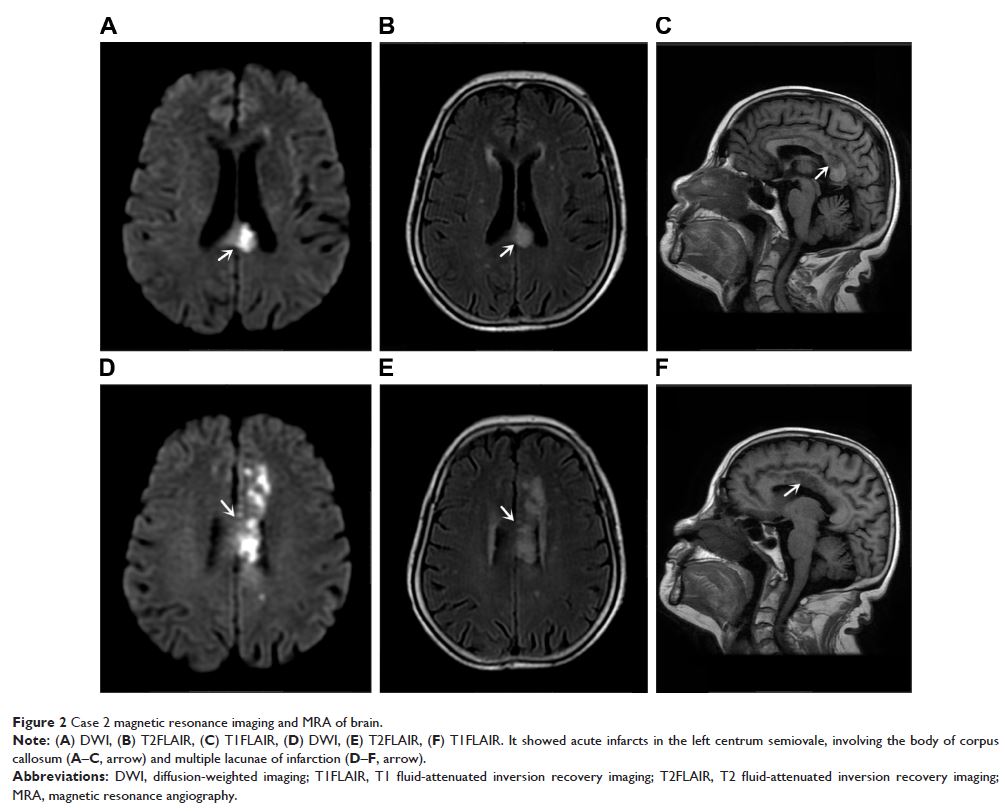

Case Series

- 作者:Jianyu Zhang, Yi Tang, Yongan Sun, Yingda Xu, Lingen Pang, Jiaojiao Li, Taotao Wu, Mingli He

- 期刊:Neuropsychiatric Disease and Treatment